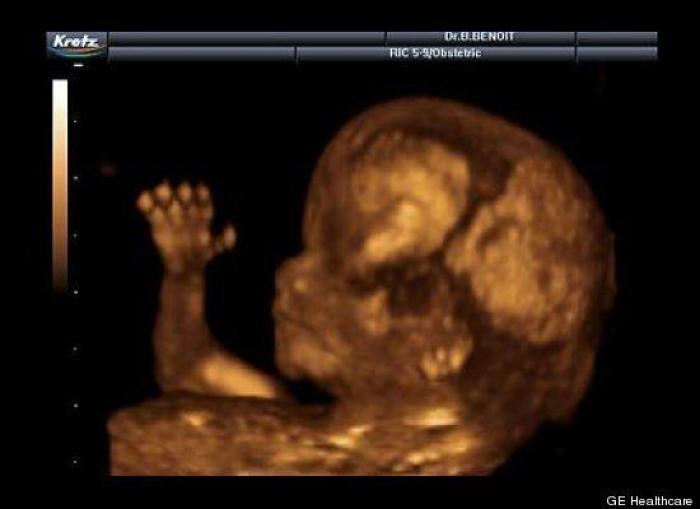

En esta galería puedes ver en fotos como es el desarrollo de un feto de semana en semana:

Desarrollo del feto, en fotos